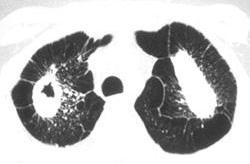

问题 男,68岁,呼吸困难,发绀,咯血1周,有40余年采矿史,请结合CT检查选择最可能的诊断 ( )

选项 A、肺脓肿 B、支气管扩张 C、矽肺 D、肺癌 E、肺结核

答案 C